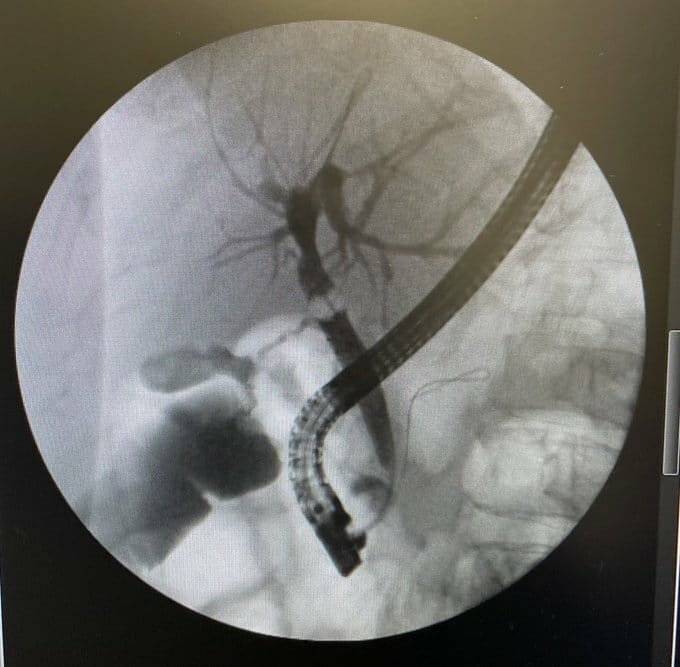

Safra yolları, karaciğer ve pankreas hastalıklarının tanı ve tedavisinde kullanılan ERCP işlemi Ağrı Eğitim ve Araştırma Hastanesi'nde ilk kez uygulandı. Gastroenteroloji Uzmanı Dr. Bayram Yeşil ve ekibi tarafından başarılı bir şekilde gerçekleşen uygulama sonucunda safra yollarında taş bulunan hasta ERCP işlemi uygulanarak sağlığına kavuştu.

Ağrı'da yaşayan 84 yaşındaki S.S hasta karın ağrısı şikayeti ile hastaneye başvurdu. Yapılan tetkikler sonucunda safra yollarında ki taşa bağlı pankreas bezi hasarı tespit edildi. Hasta hastaneye yatırılarak tedavi altında alındı ve hastaya ERCP yapılarak safra yollarındaki taş endoskopik olarak çıkarıldı. İşlemi gerçekleştiren Gastroenteroloji Uzmanı Dr. Bayram Yeşil; " ERCP işlemi Türkiye'de belli merkezlerde yapılmaktadır. ERCP, Safra yolları, karaciğer ve pankreas bezinin bir takım hastalıklarında tanı ve tedavisinde kullanılan ileri gastroenterolojik işlemlerden biridir. Endoskopik olarak gerçekleştirilen bu işlemde, ameliyata gerek kalmadan hastanın safra yollarına girilerek işlemler yapılmakta ve safra yollarında ki taşlar temizlenmektedir. Safra yollarında taş bulunan hastamızın safra yollarını temizleyerek başarılı bir işlem gerçekleştirdik. Hastamızın servisteki takibi devam etmektedir. Şu anda bu işleme ihtiyacı olan 6 hastamızın servis takipleri devam etmektedir ve bu hastalarımızın da safra yollarında ki taşlar ERCP ile temizlenecektir. Daha önce bu hastalarımızı çevre illere sevk etmek zorunda kalıyorduk. Bugünden itibaren hastalarımızı sevk etmeden işlemlerini hastanemizde yapacağız. ERCP işlemi için teknik ihtiyaçlarımızın hızlıca tamamlanmasını ve bu işlemin hastanemizde yapılmasını sağlayan başta il sağlık müdürümüz Dr. Öğr. Üyesi Coşkun Daharlı'ya, başhekimimiz Opr. Dr. Cengiz Kazdal'a ve hastane yönetimimize teşekkür ederim" dedi.